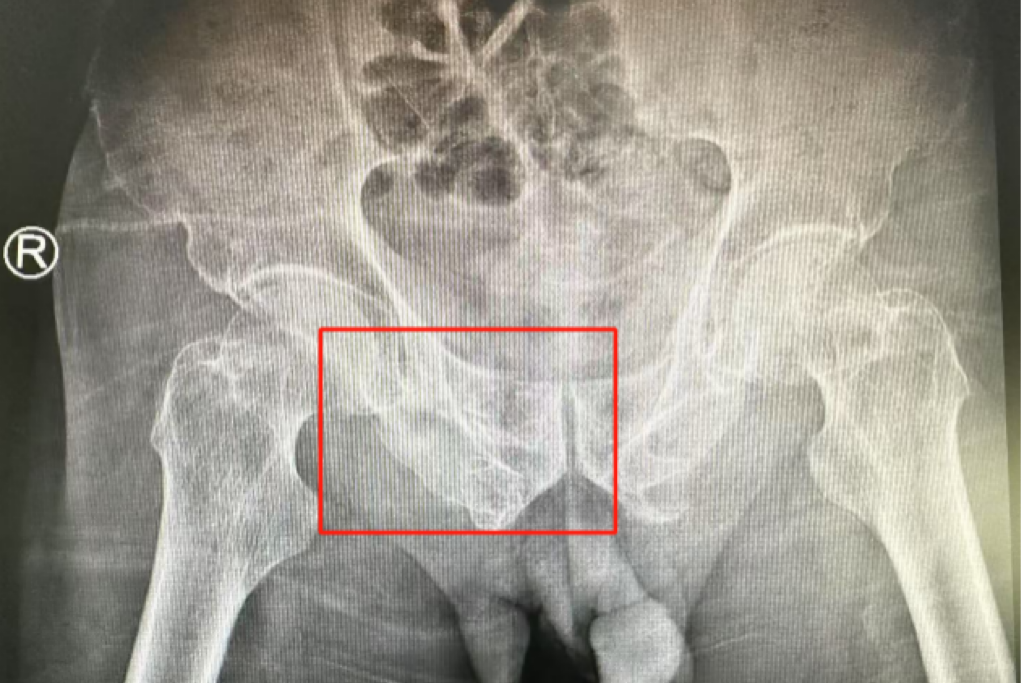

術(shù)前影像學(xué)顯示,患者的左側(cè)骶骨骨折,右側(cè)恥骨骨折、髂骨骨折,骨盆骨折分型為C型,老年脆性骨盆骨折分型為IV型,是極度不穩(wěn)定型的前環(huán)骨折和雙側(cè)后環(huán)骨折。所幸沒有明顯的骨盆出血或內(nèi)臟損傷的表現(xiàn)。

術(shù)后第二天,醫(yī)生團隊復(fù)查X片顯示螺釘植入位置非常滿意,骨折基本達(dá)到穩(wěn)定復(fù)位,同時,復(fù)查的全血細(xì)胞計數(shù)中,血紅蛋白指數(shù)為102g/L。術(shù)后第三天,在智能骨科病房護理團隊及康復(fù)師的指導(dǎo)和護理下,王大爺可以坐立在床上。術(shù)后第四天,王大爺迎來了出院日,“得虧有了這么先進(jìn)的醫(yī)療技術(shù),讓我還能下地行走,謝謝你們!”

螺釘植入位置非常滿意

王大爺身體恢復(fù)良好